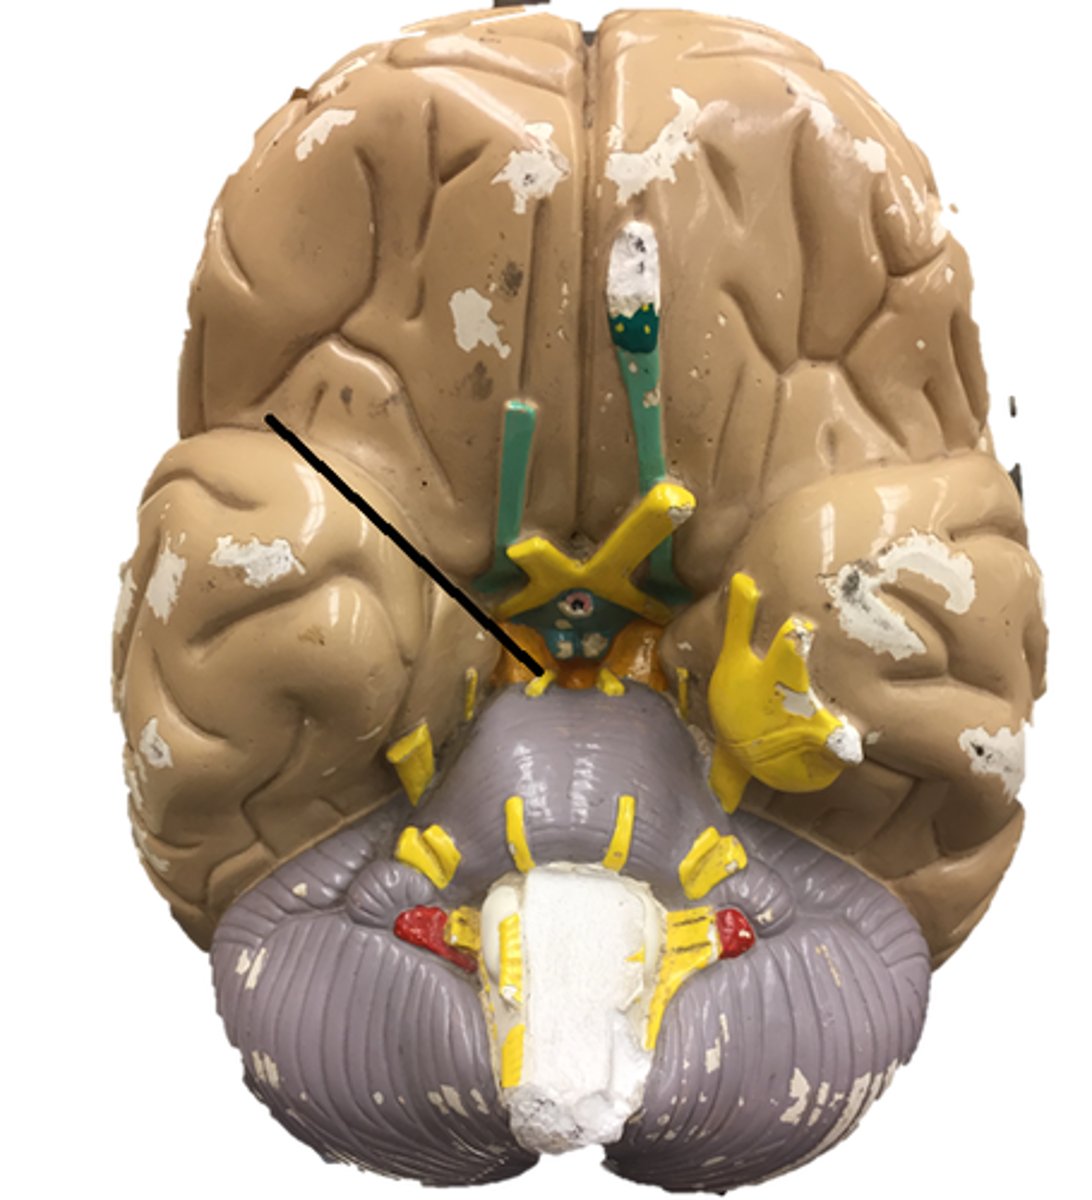

optic chiasm

olfactory nerve

optic nerve

oculomotor nerve

trochlear nerve

trigeminal nerve

abducens nerve

facial nerve

vestibulocochlear nerve

glossopharyngeal nerve

vagus nerve

accessory nerve

hypoglossal nerve

optic tract